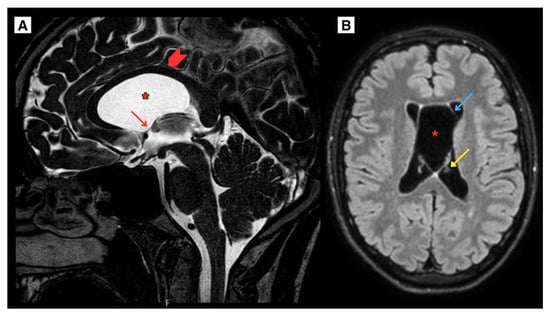

Figure 2.

(A) T2W sagittal sequence. The corpus callosum was elevated and displaced, with the fornix compressed. No significant optic nerve deformation or impact on the hypothalamus was observed. Wider lateral ventricles with the left temporal horn dilated up to 5 mm. (B) T2W-FLAIR axial sequence with the CSP and CV cysts showed the maximum diameter measuring approximately 30 mm covering the intraventricular foramen. Arrowhead—corpus callosum, Red arrow—intraventricular foramen, Blue arrow—cavum septum pellucidum wall, Yellow arrow—choroid plexus of lateral ventricle, Asterisk—cavum septum pellucidum and cavum vergae cyst.

As the CSP and CV cysts enlarged, they covered the intraventricular foramen, contributing to significant obstruction of the CSF pathways. This resulted in cerebrospinal fluid (CSF) flow disturbances, with almost no visible CSF flow through the cerebral aqueduct and the central spinal canal. Additionally, weakened CSF flow was noted dorsal to the medulla oblongata, while increased flow was observed ventrally to the medulla oblongata (Figure 3). These findings illustrate the physiological consequences of the progressive cyst growth and their role in the development of obstructive hydrocephalus.

Figure 3.

MRI of the brain (A) CSF sagittal sequence (2024) of CSP and CV cysts covering the intraventricular foramen resulted in CSF flow disturbances, with almost no visible CSF flow through the cerebral aqueduct and the central spinal canal. Additionally, weakened CSF flow was noted dorsal to the medulla oblongata while increased flow was observed ventrally to the medulla oblongata. (B) CT brain scan in axial plane (2024) post endoscopic fenestration of the right side of the CSP cyst revealed brain tissue edema and air present at the surgical access site in the right frontal lobe. The CSP maximum diameter measured approximately 21.2 mm. Red arrow—interventricular foramen, Blue arrow—pneumocranium, Yellow arrow—septum pellucidum wall, Asterisk—septum pellucidum cyst.